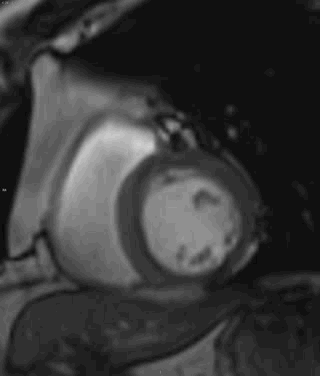

舒张末期

收缩末期

最后的收缩和舒张末期主要是对比看一下左室下侧壁的运动情况

电影:左室中央段-心尖段下侧壁运动减低,心肌内见片状高信号